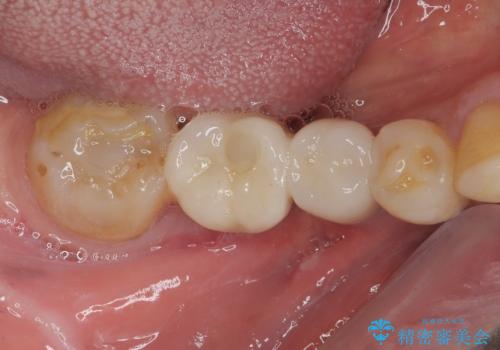

奥歯がしみる オールセラミッククラウンによる奥歯のむし歯治療